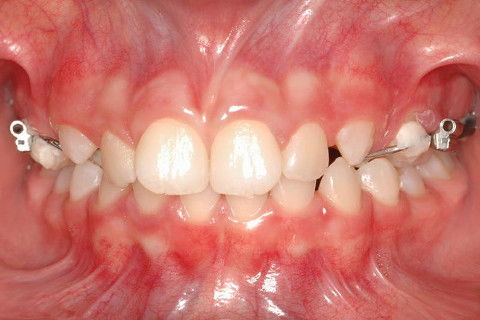

Caso clínico de Ortopedia Funcional dos Maxilares     Há 15 anos

FRONTAL INICIAL

PACIENTE CLASSE II.

ATRESIA DE MAXILA.

SOBREMORDIDA.